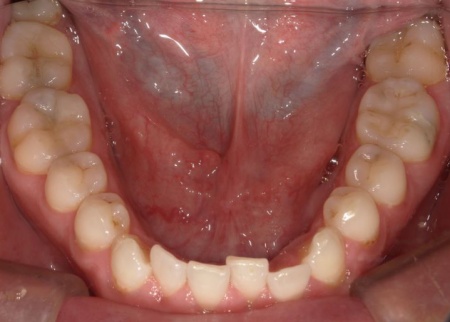

40代男性 長年放置していた虫歯や根尖性歯周炎などの口腔トラブルを全体的に治療した症例

「虫歯を長年放置してしまったので治療をしたい。また、見た目や噛み合わせの改善などを含めた、全体的な治療も行いたい」とご相談いただきました。

患者様は、10年ぶりに歯科医院を受診したとのことです。

レントゲン撮影をして詳しく検査したところ、複数の小さな虫歯が見られました。

また右上奥歯には、歯根の先に炎症が起きて膿が溜まる根尖性(こんせんせい)歯周炎が認められます。

さらに、左上奥歯(第1大臼歯)は温存が難しい状態でした。

以上のことから、口腔内を全体的に治療する必要があると診断しました。